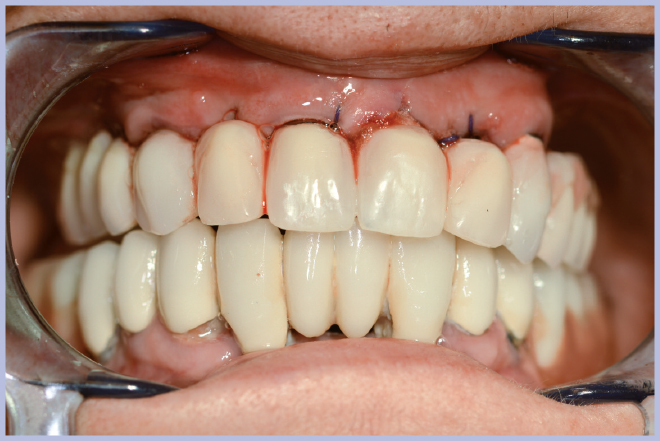

La nuova protesi, realizzata in materiale composito sul modello di quella pre-esistente (Fig. 9), è stata poi ribasata in bocca sull’armatura di rinforzo fissata ai monconi (Fig. 10). Ad indurimento avvenuto della resina per ribasature, si sono rimosse le viti e si è rifinita la protesi. L’operazione di rifinitura da parte del tecnico è di grande importanza, perché si deve il più possibile ridurre l’estensione della flangia vestibolare al fine di favorire una buona detersione da parte del paziente.

La semplicità della componentistica Leone ha permesso di completare l’intero trattamento in circa 6 ore e mezzo, consegnando alla paziente la protesi ultimata nella stessa giornata della chirurgia (Figg. 11-13).

- Fig. 10 – Fissaggio della protesi sulla struttura metallica